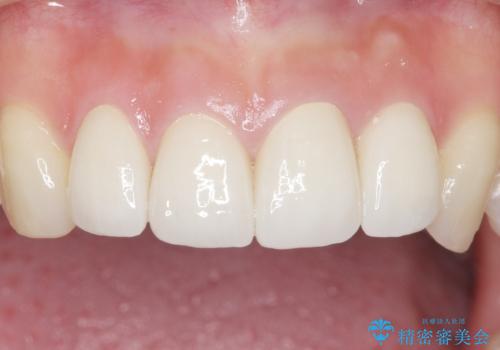

綺麗な仕上がりに喜んで頂けました。

患者様のご希望により、クラウン作製前にオフィスホワイトニングを行いました。

今後ホワイトニングを継続し天然歯をより白くしていく予定とのことで、クラウンのお色味は隣在歯よりやや白めにオーダーしております。

クラウンの種類:オールセラミッククラウン スタンダード